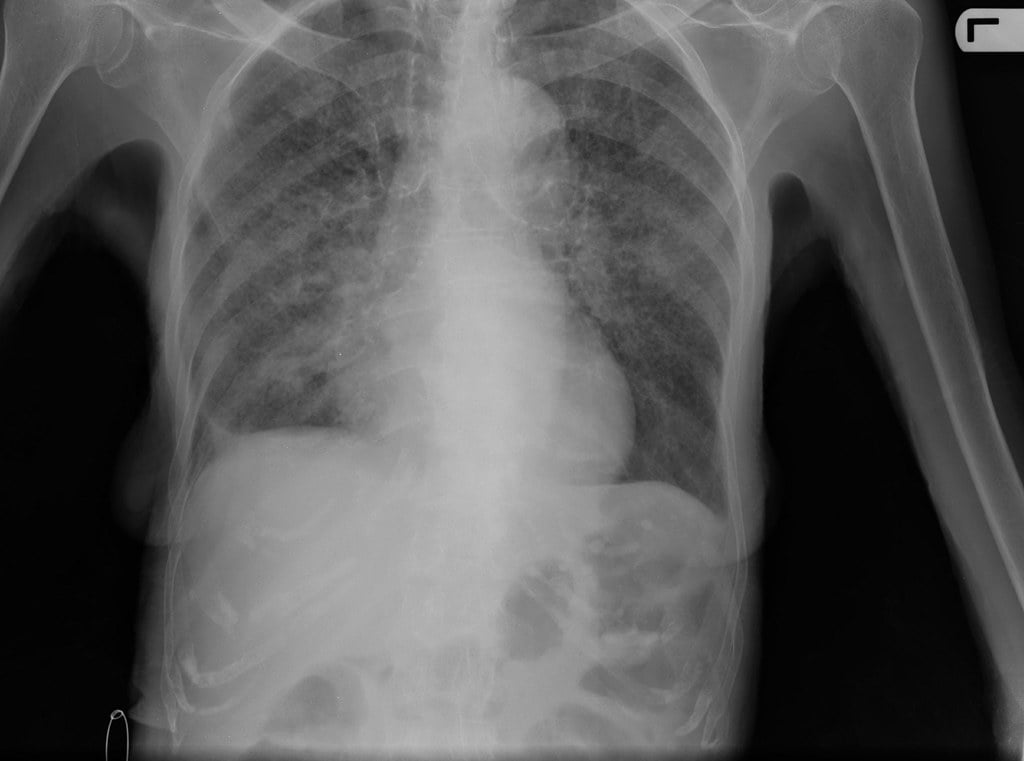

Comment un investissement soutenu peut aider à mettre fin à la tuberculose

Thoko Elphick Pooley de la Fondation Gates et Fodé Danfakha du Programme de lutte contre la tuberculose au Sénégal proposent un plan d'élimination de cette maladie.